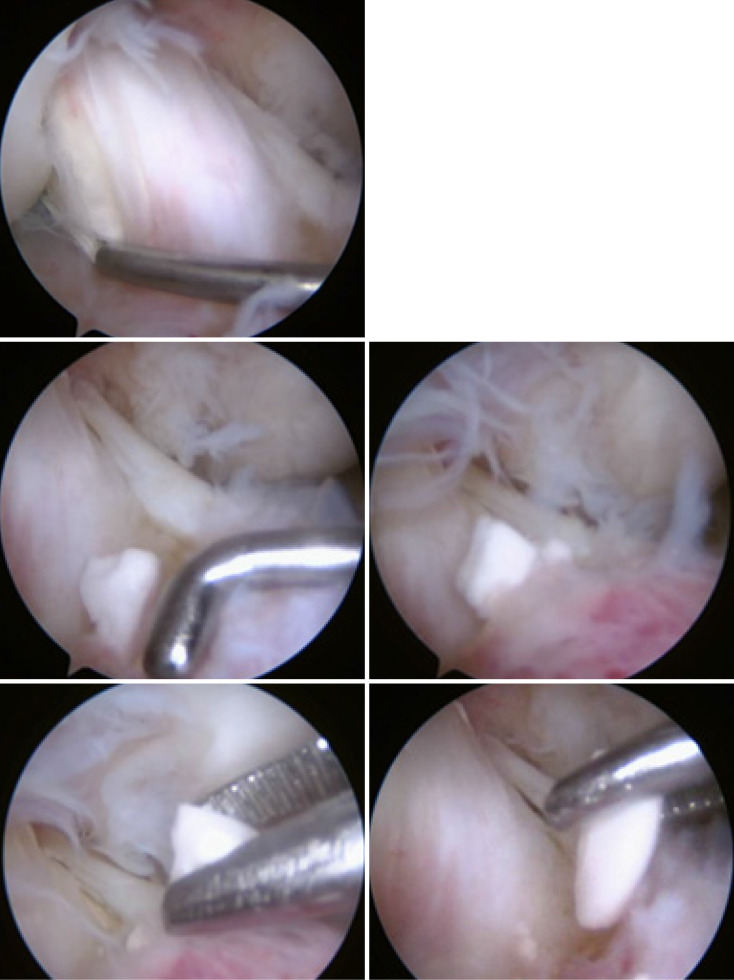

Case summary: A 26-year-old male presented with knee pain and swelling one year after ACL reconstruction using a hamstring graft and bioabsorbable tibial interference screw. The patient had been engaged in rigorous physical activity as part of military training. Clinical examination revealed mild effusion without instability, and imaging showed screw breakage with intra-articular migration. Therapeutic arthroscopy confirmed intact graft tension, and broken screw fragments were removed successfully. The patient resumed normal activity two weeks after surgery.